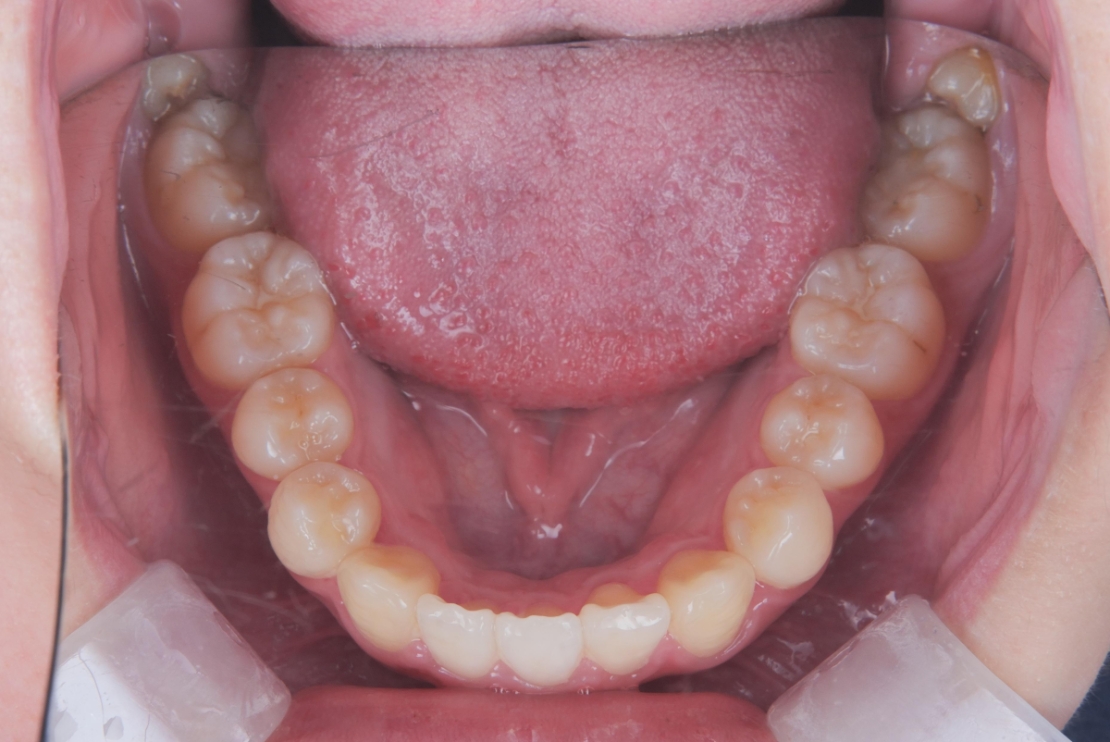

AFTER

治療は、マウスピース矯正インビザラインにて矯正治療を行い、歯列全体のバランスを考慮しながら計画を立てました。治療期間は1年4ヶ月で、歯並びがきれいに整っています。

| 施術内容 | 歯全体のマウスピース矯正システム「インビザラインアドバンス」を用いた治療 |

| 治療期間 | 1年4ヶ月 |